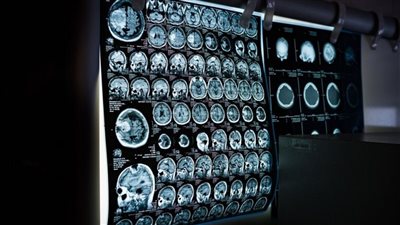

ووفقًا لـ الدراسة البريطانية يعمل الشعور بالتوتر نتيجة تفاعل وظيفة المُعجنات داخل الجسم على انخفاض تدفق الدم والأكسجين الذي يصل إلى الدماغ، موضحة أن تناول هذه الأطعمة الدهنية خلال فترات الضغط النفسي تزيد من إجهاد الجسم بشكل كبير.

وأوضحت نتائج الدراسة أن تناول هذه المعجنات، تقلل من أكسجين الدماغ وضعف وظائف الأوعية الدموية لدى البالغين، مما قد يتسبب في حدوث نوبة مرهقة عقليًا.